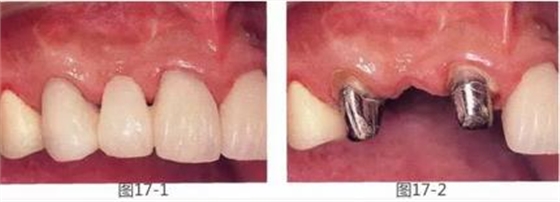

圖17-1,2 術(shù)前。右上2的橋體部唇側(cè)存在凹陷。

圖17-3 咬合面照片。